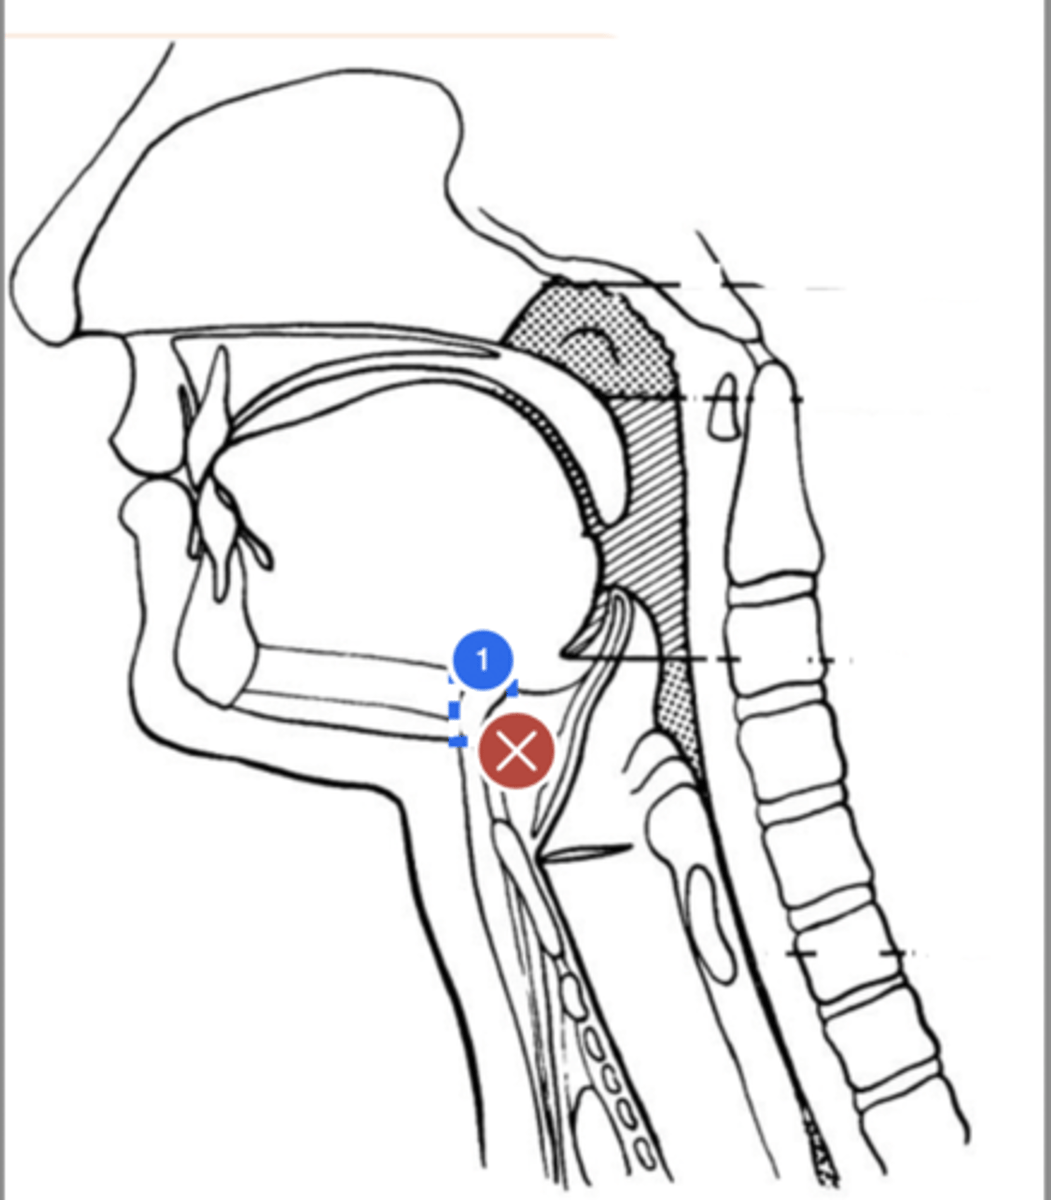

Label Nasopharynx (lateral view)

Label Nasal cavity (lateral view)

Label oropharynx (lateral view)

Label hypopharynx/ hylolarynx

Label tongue (lateral view)

Label soft velum/ palate (lateral view)

Label hard palate (lateral view)

Label mandible (lateral view)

Label base of tongue (lateral view)

label hyoid bone (lateral view)

Label epiglottis (lateral view)

label Line of true vocal folds (lateral view)

label Thyroid cartilage (anteriorly) (lateral view)

Label posterior cricoid (lateral view)

Label esophagus (lateral view)

label anterior tongue (lateral view)

Label posterior/ back of tongue (lateral view)

Label velum/ soft palate (lateral view)

Label thyroid cartilage (lateral view)

Label trachea (lateral view)

Label upper esophageal sphincter (lateral view)

Label posterior pharyngeal wall (lateral view)